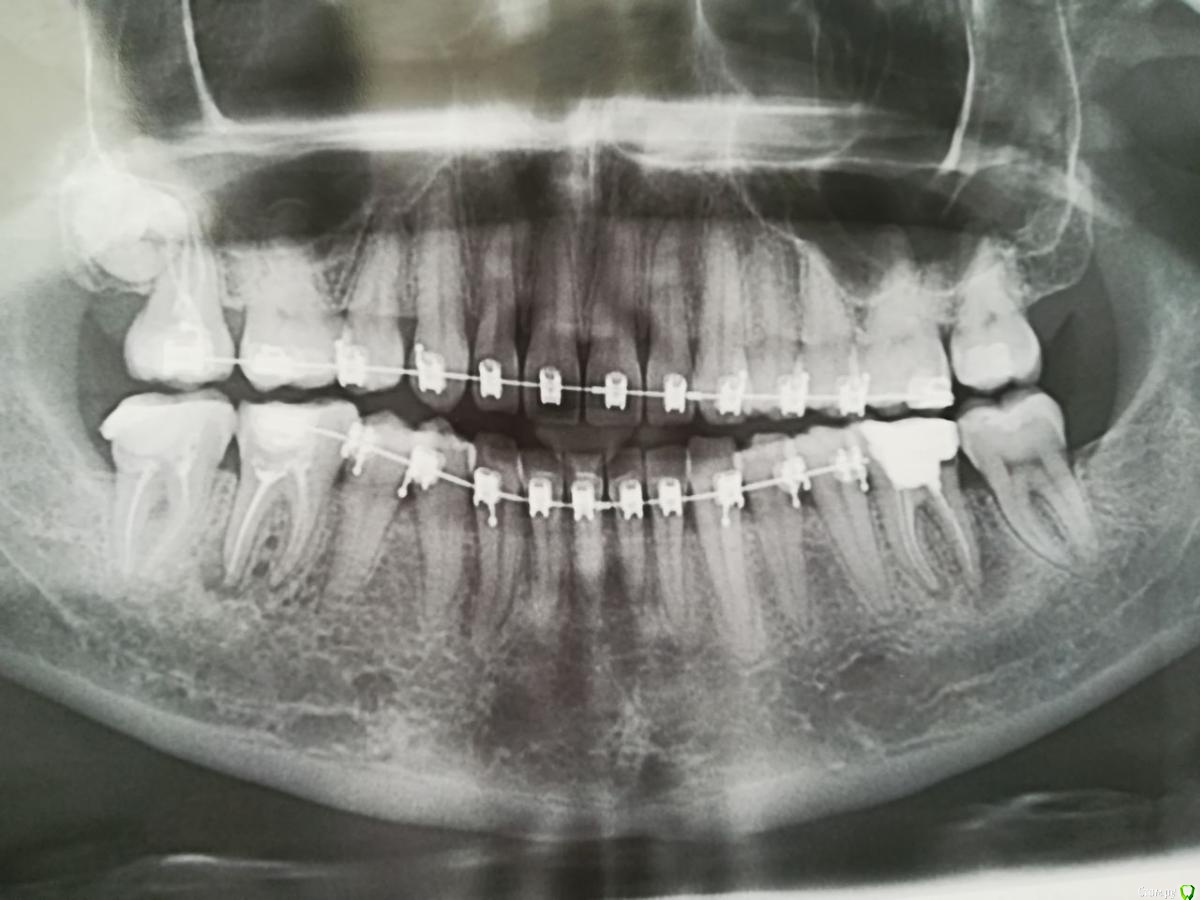

Tansky Опубликовано 18 марта, 2020 Автор Поделиться Опубликовано 18 марта, 2020 снимки - пара отпг до орто и актуальная, от 17.03.2020пара кт, в области интереса 3.6 и 4.7, разные снимки Ссылка на комментарий

Tansky Опубликовано 18 марта, 2020 Автор Поделиться Опубликовано 18 марта, 2020 разные проекции и описание заключения. прицельные rg есть еще по тому же зубу разных времен, но это надо искать дома и фоткать с негатоскопа или днем на свет Ссылка на комментарий

Tansky Опубликовано 11 мая, 2020 Автор Поделиться Опубликовано 11 мая, 2020 закрывайте тему, зуб перелечен и поставлена коронка всем неравнодушным спасибо! 1 Ссылка на комментарий